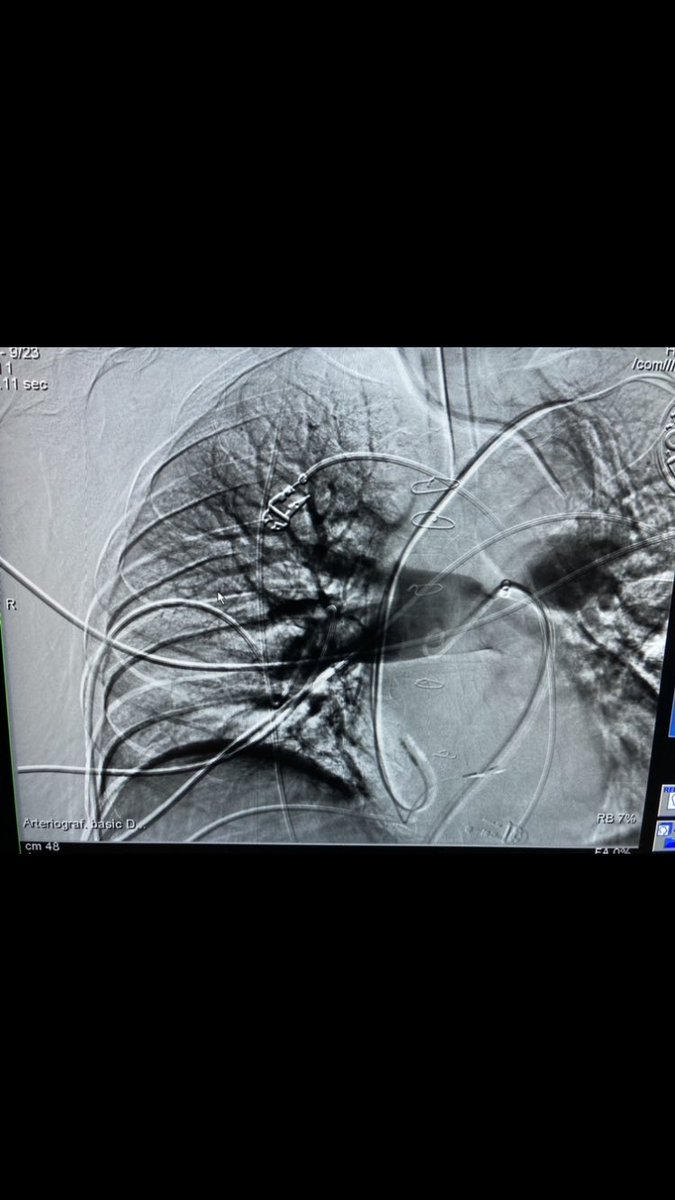

Patient with malignant SVC syndrome, IVC stenosis, and venous thrombosis. Thrombectomy performed with CAT 12 lightning. Kissing covered stents placed in SVC. Fantastic result by Emily Cuthbertson Corey Hanrahan. Temple Radiology Residents SIR ECS SIR RFS Penumbra Vascular #irad

Patient with malignant SVC syndrome, IVC stenosis, and venous thrombosis. Thrombectomy performed with CAT 12 lightning. Kissing covered stents placed in SVC. Fantastic result by <a href="/DrECuthbertson/">Emily Cuthbertson</a> <a href="/chanrahan21/">Corey Hanrahan</a>. <a href="/TempleRadRes/">Temple Radiology Residents</a> <a href="/SIR_ECS/">SIR ECS</a> <a href="/SIRRFS/">SIR RFS</a> <a href="/PenVascular/">Penumbra Vascular</a> #irad